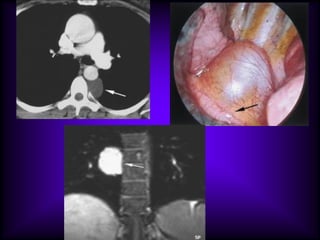

Mediastinal Cysts

The CT features of benign

mediastinal cyst are

(a) a smooth, oval or tubular mass with a well-

defined thin wall that usually enhances after

intravascular administration of contrast

material,

(b) homogeneous attenuation, usually in the

range of water attenuation (0–20 HU),

(c) no enhancement of cyst contents, and

(d) no infiltration of adjacent mediastinal

structures.

Cysts that contain serous fluid typically have

long T1 and T2 relaxation values, which

produce low signal intensity on T1-weighted

MR images and high signal intensity on T2-

weighted images.

Because cysts containing nonserous

fluid can have high attenuation at CT,

they may be mistaken for solid

lesions. MR imaging can be useful in

showing the cystic nature of these

masses because these cysts continue

to have characteristically high signal

intensity when imaged with T2-

weighted sequences regardless of the

nature of the cyst contents

Pericardial Cyst